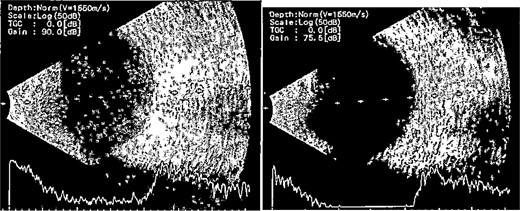

Patient 2: A 69-year-old Saudi female experienced severe right eye pain after surgery on the same day as patient 1. Visual acuity was reduced to hand motions, and examination showed conjunctival ciliary injection, corneal edema, and hypopyon (Fig. 3). B-scan confirmed vitritis (Fig. 4). She received similar emergency interventions as patient 1.

Surgical microscope examination showing hypopyon, chemosis, ciliary, and conjunctival injection in patient 2.